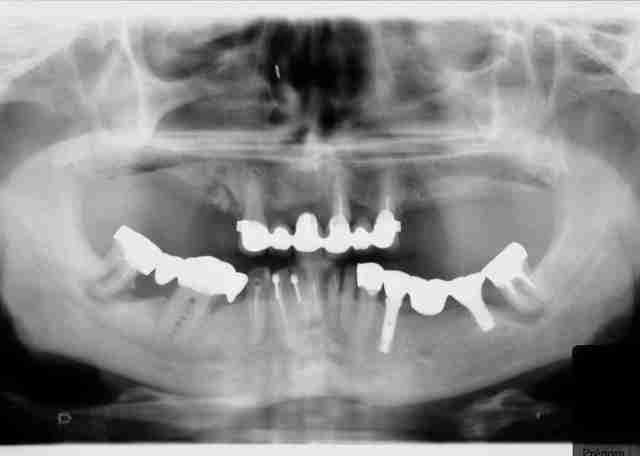

Patient adressé pour traitement d'une periimplantite à la mandibule.

J'étais plus qu'heureux qu'il ne s'agissait pas des implants maxillaires!! J'aurais eu peur de lui crevé l'oeil !! ;-)

Au risque de dire encore une anerie: dans "l'oeil" gauche, il n'y aurait pas un morceau de greffe osseuse qui se détacherait?

mais non c'est juste une fracture du plancher orbitaire, toi qui pensait que c était grave!!!

il a eu chaud

ça c'est un festival

c'est grave docteur ?

le haut a été fait soi disant il y à 2 ans

ça c'est du plan de traitement.